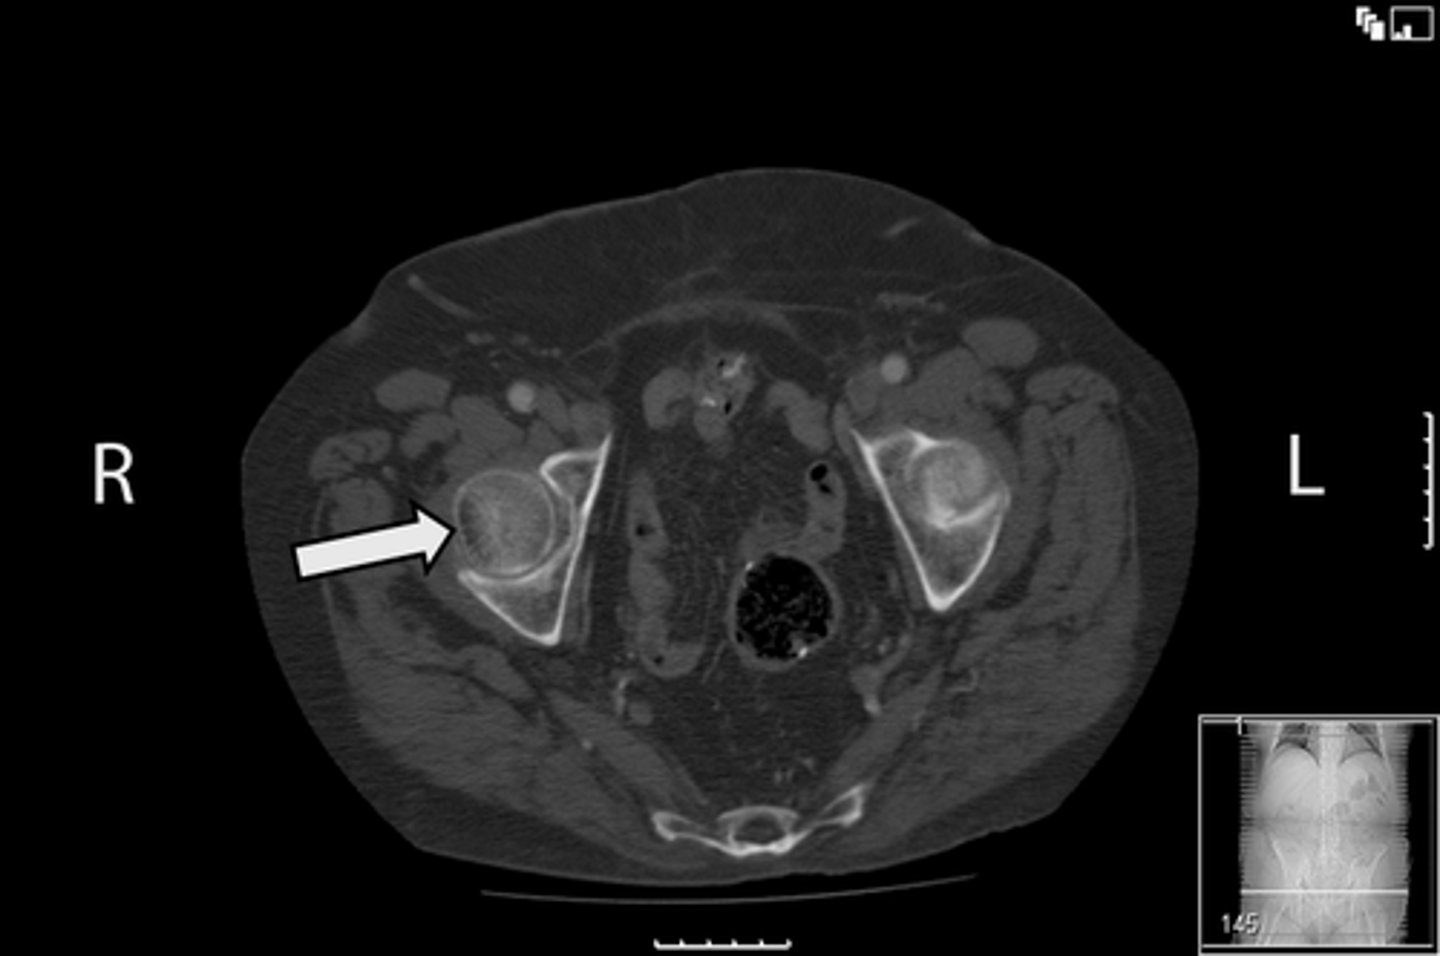

Axial bony pelvis CT

What is the image?

L acetabulum

What is indicated in the image?

L femoral head

L piriformis muscle

R femoral head

R piriformis muscle

R acetabulum (posterior part)

Sacrum